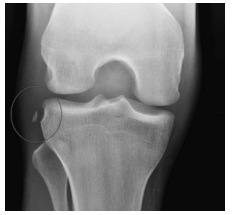

Um paciente de 22 anos de idade realizou torção de joelho direito jogando futebol há um dia. Apresenta-se com edema articular importante, o que impede a realização apropriada das manobras do exame físico. Joelho difusamente doloroso à palpação.

Com base no caso clínico apresentado e na imagem de radiografia, é correto afirmar que se trata de uma fratura de